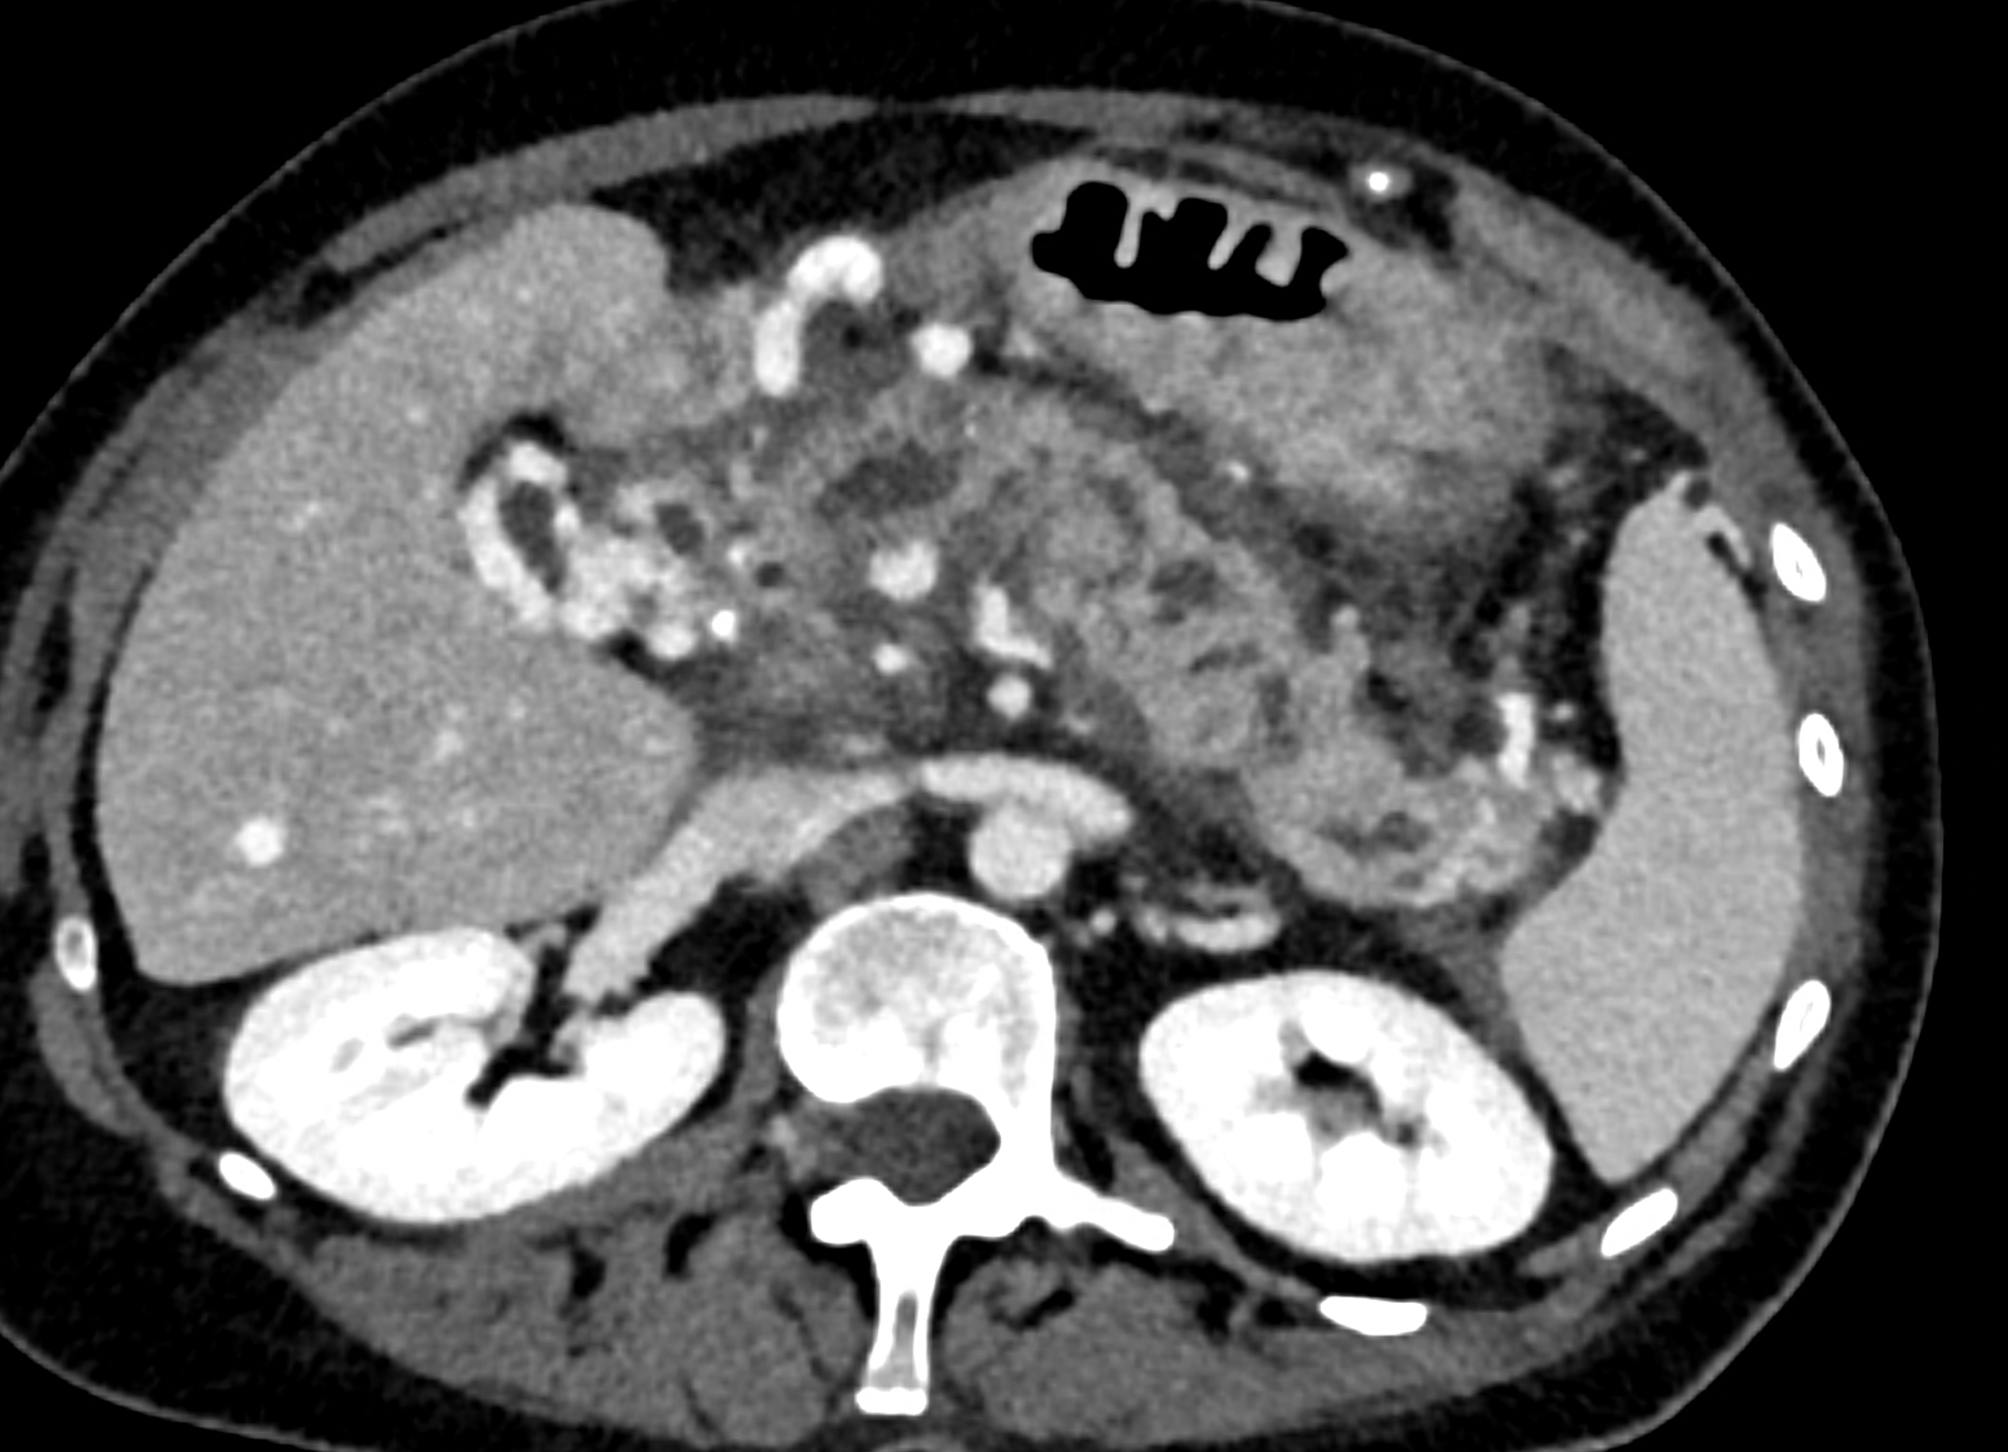

A patient with chronic pancreatitis and chronically occluded portal vein. The bile ducts have a significantly dilated wall, from the trunk, through the stump of the cystic duct, to the right and especially the left branch of the hepatic duct. At the same time, a large pseudocyst in the pancreas, dilatation of the pancreatic duct, and chromic occlusion of the superior mesenteric vein, splenic vein, and portal vein trunk are evident. Along with portal biliopathy, there is also arixy of the cardia and esophagus, as well as cavernous remodeling of the portal circulation itself.

dilated collaterals in hepatoduodenal ligament partially portal biliopathy, partially cavernous transformation

reconstruction paralel to hepatoduodenal ligamant